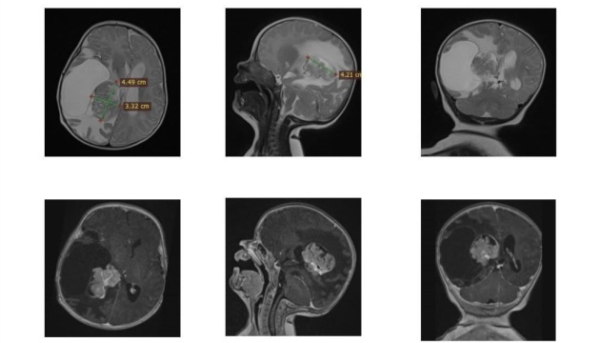

Підкреслюється, що у двомісячного малюка з Рівного виникла небезпечна неоплазма у правому бічному шлуночку головного мозку, що становила загрозу для її існування. Єдиним способом урятувати дитину було складне нейрохірургічне втручання.

«Видалення новоутворення у такої крихітної пацієнтки саме по собі є вкрай ризикованим. Утворення знаходилося в області судинного сплетіння з інтенсивним кровопостачанням, а відповідно, з великим ризиком значної втрати крові. Крім того, пухлина прилягала близько до ділянки, яка відповідає за рухи. Тому хірургічне втручання вимагало максимальної точності та скрупульозної підготовки», – відзначив очільник Клініки дитячої нейрохірургії Михайло Ловга.